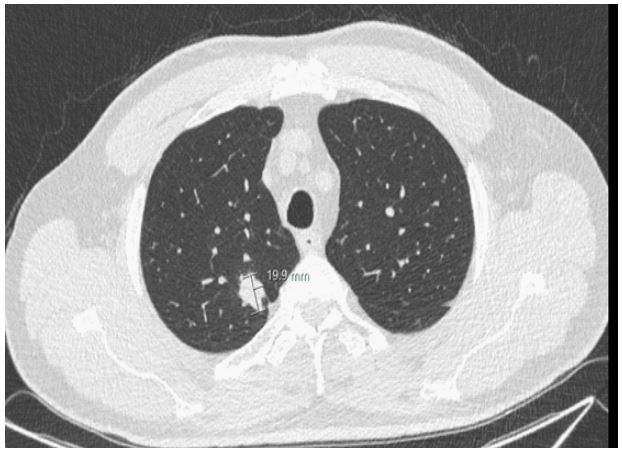

The MA test results of the case report subject indicated a response profile to tumor-associated peptides corresponding wells with a subject with LC malignancy. As a result, the case report subject was clearly suspected to have LC. He was referred for further clinical investigation at the Rambam Medical Center Haifa, Israel. As the Liquid ImmunoBiopsy™ MA test results showed a high-risk metabolic profile for malignancy, the patient was referred to low-dose computed tomography (LDCT) that revealed a 20 x 19 x 16 mm right upper lobe mass with no hilar or mediastinal lymphadenopathies (Figure 2). He underwent a PET scan examination which showed increased 18F-fluorodeoxyglucose (FDG) uptake only in the right upper lobe mass, thus raising a high suspicion for early lung cancer (Figure 3). After a preoperative evaluation that revealed normal lung function test, the patient underwent a uniportal thoracoscopic right upper lobectomy (VATS) with mediastinal lymph node dissection. Patient had uneventful recovery from the surgery and was discharged on postoperative day 2. Pathology confirmed a diagnosis of stage IA (T1b N0 m0) well differentiated adenocarcinoma, 1.5 cm in diameter, with 9 mediastinal and hilar lymph nodes without evidence of metastasis.

Figure 2: LDCT image Low-dose CT scan showing a solid lesion measuring 20 x 19 x 16 mm in size, in the right upper lobe.

Recently, we recruited to the healthy control group of a clinical trial study a subject who does not have a smoking history and does not belong to any high-risk group for lung cancer. The MA-LC ImmunoBiopsy™ test’s result of his blood sample indicated a response profile to tumor associated peptides of a subject with malignancy, and this blood donor was clearly suspected to have LC. The person was referred for further clinical investigation which included LDCT and PET-CT screening. LDCT showed a suspected lesion (Figure 2). The PET-CT image showed that this lesion is highly suspected to be malignant (Figure 3). Following these findings, he underwent thoracoscopic right upper lobectomy. The malignant tumor was removed and identified as NSCLC adenocarcinoma stage IA. The early detection of lung cancer by the MA-LC ImmunoBiopsy™ test and the subsequent surgery treatment to remove the malignant tumor is expected to lead to a high probability of a full recovery from the LC. We reported4 that the MA-LC ImmunoBiopsy™ test provides results within five hours of receiving the blood sample for MA-LC. The analytical sensitivity of the test is high, with a lower limit of quantification (LLOQ) of 0.000119 (d/minute) in change of acidity over time. It specifically quantifies glycolysis, which is a biomarker for the activation level of immune cells that are re-exposed in-vitro to lung TAA stimulants. Currently, liquid biopsy is mainly utilized as an auxiliary tool in lung cancer diagnosis, when a LDCT detects an abnormality. We believe that the non-invasive MA-LC ImmunoBiopsy™ test, with its low material costs, fast results, and a patient-friendly blood test character, has a potential to be an integral part of lung cancer mass screening programs for high risk populations first and foremost, but as shown in this case, also for a broader population without high risk.